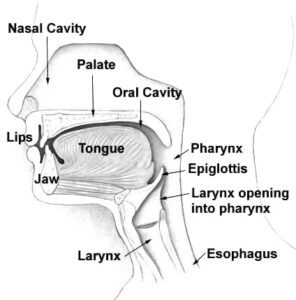

Cleft Lip and Palate

Cheatsheets

2

Mnemonics

1

Images

9

Picmonic

0